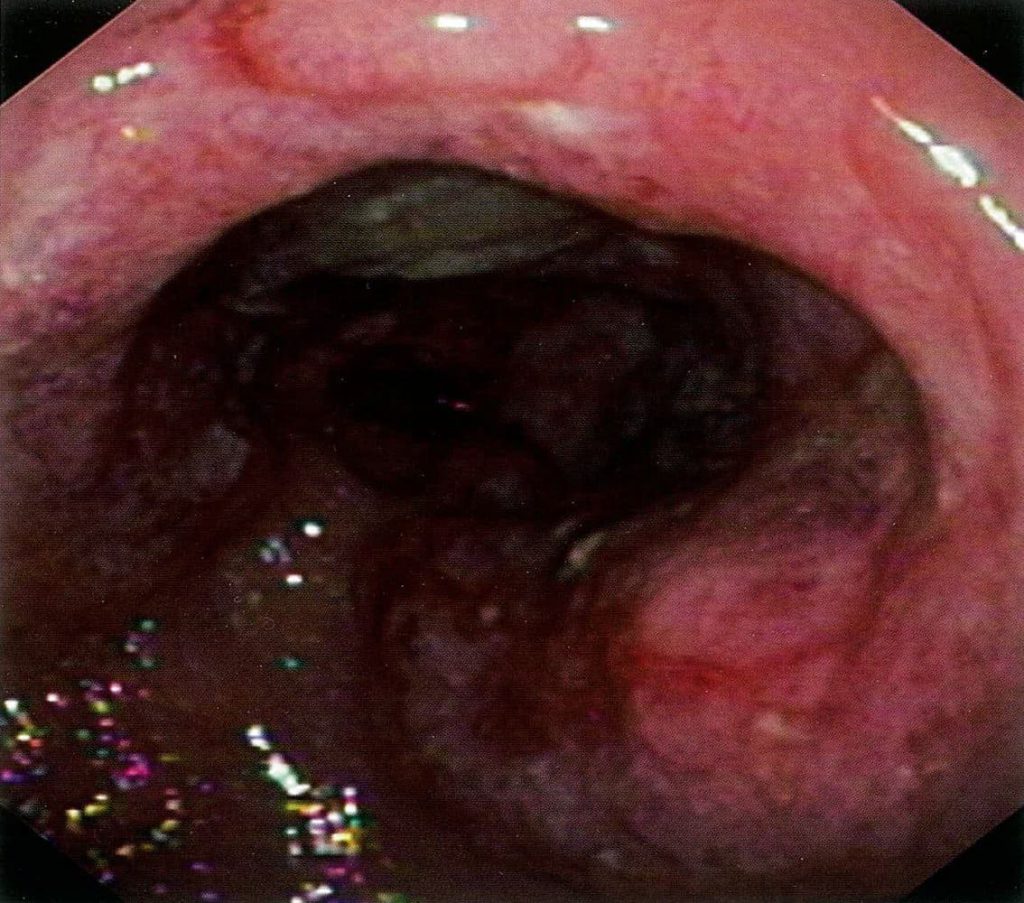

کولیت اولسراتیو (UC)

کولیت اولسراتیو (UC) نوعی بیماری التهابی روده (IBD) است که با التهاب مزمن مخاطی رکتوم، کولون و سکوم مشخص میشود. علائم متداول عبارتند از اسهال خونی، درد شکم و تب. یافتههای آزمایشگاهی به طور معمول نشانگرهای التهابی افزایش یافته و وجود آنتیبادیها (p-ANCA) را نشان میدهند.